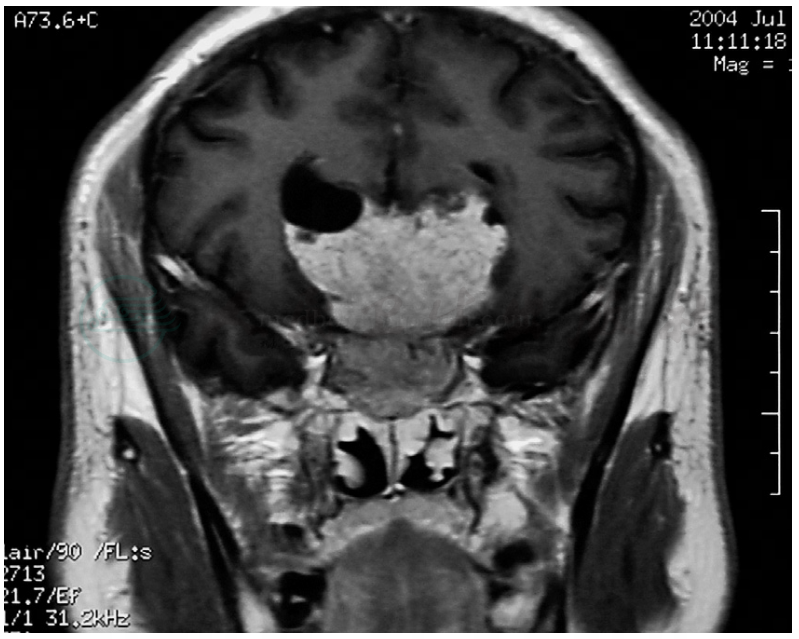

图23脑膜瘤

MR冠状位T1WI增强扫描。蝶窦及鞍上可见明显增强肿物,可见脑膜尾征(→)